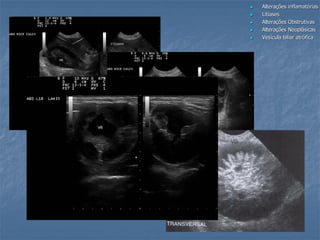

Obstrução Biliar Extra-Hepática

Obstrução vias biliares extra hepáticas

sem dilatação da vesícula biliar

felino